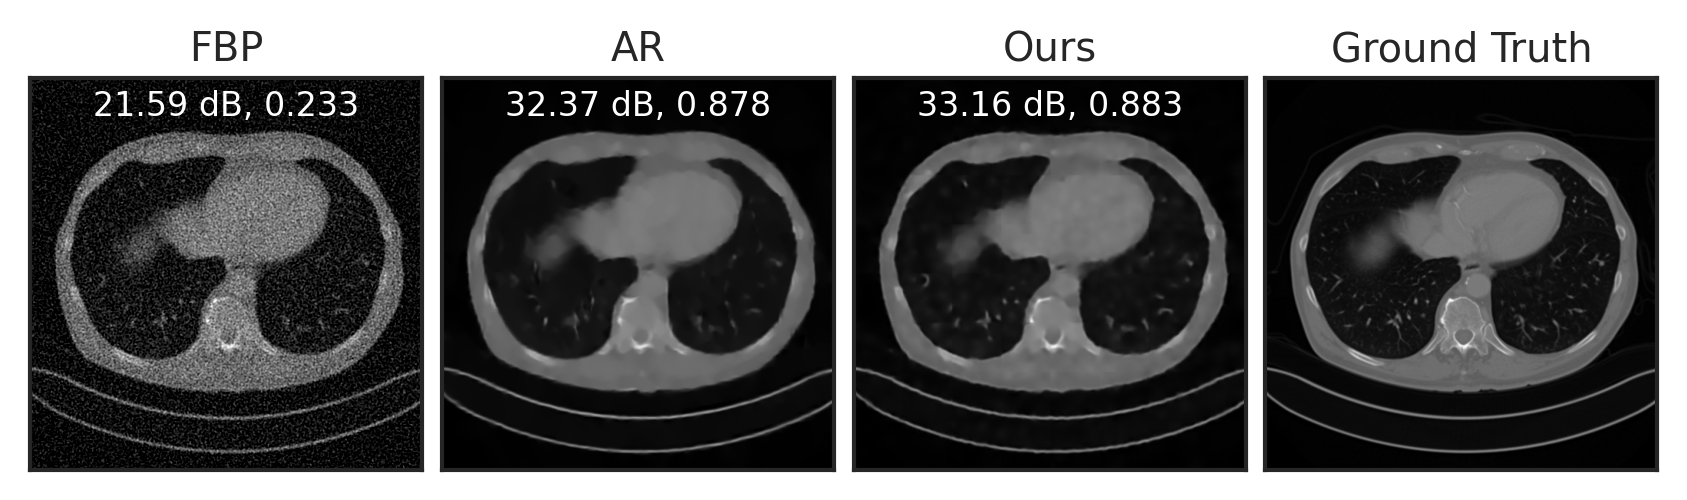

We train LPN on the public Mayo-CT dataset mccollough2016tu of Computed Tomography images, and evaluate it for two inverse tasks: sparse-view CT reconstruction and compressed sensing. For sparse-view CT reconstruction, we compare with the baseline filtered back-projection (FBP) approach willemink2019evolution, the adversarial regularizer (AR) lunz2018adversarial, a learning-based approach with explicit regularizer, and the improved, unrolling-based AR (UAR) mukherjee2021end. UAR is trained to solve the inverse problem for a specific measurement operator (i.e. task-specific), while both AR and LPN are generic regularizers that are applicable to any forward operator (i.e. task-agnostic). In other words, the comparison with UAR is not completely fair (as it is a task-specific method), but we include it here for comparison.

Following Lunz et al. [62], we simulate CT sinograms using a parallel-beam geometry with 200 angles and 400 detectors, with an undersampling rate of . See Section E.4 for experimental details. As visualized in Figure 5(a), compared to the baseline FBP, LPN can significantly reduce noise in the reconstruction. Compared to AR, LPN result is slightly sharper, with higher PNSR. The numerical results in Table 2 show that our method significantly improves over the baseline FBP, outperforms the unsupervised counterpart AR, and performs just slightly worse than the supervised approach UAR – without even having had access to the used forward operator. Figure 5(b) and Table 2 show compressed sensing results with compression rates of and . LPN significantly outperforms the baseline and AR, demonstrating much better generalizability to different forward operators and inverse problems.